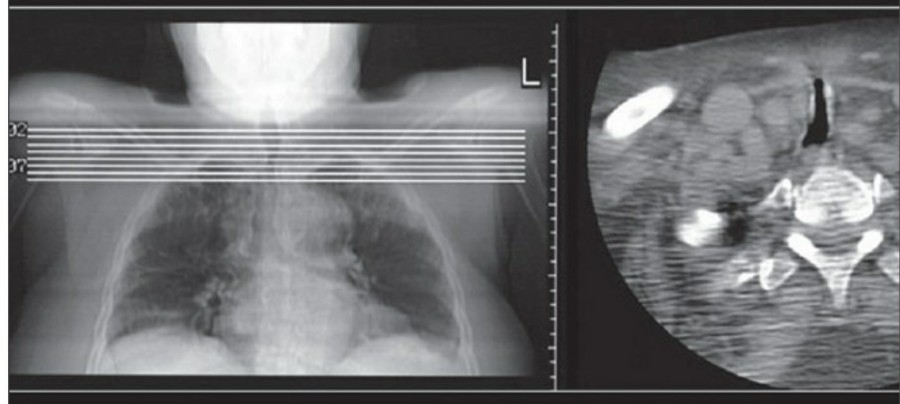

잘못 위치한 entdotracheal tube는 호흡기능에 심각한 영향을 미치는 데 약 10%의 환자에서 보고되고 있다. 따라서 ET tube를 갖고 있는 환자에서는 매일 chest radiographt의 확인이 필요하다. ET tube의 올바른 위치는 mid-trachea lvel에서, carina로부터 약 5cm 위이다. 환자의 고개가 flextion 혹은 extention 하면서 tip의 위치가 바뀔 수 있는데, 가장 최소한의 안전한 위치는 carina로부터 2cm 위이라고 할 수 있다.

Chest X ray 사진에서 carina 위치를 정확히 알 수가 없다면 이전 사진과 비교해서 그 위치를 가늠해 볼 수 있겠지만, upper dorsal spine을 확인해 봄으로써 ET tube의 tip을 확인할 수 있다. Carina는 보통 T4-T5 사이에 위치하므로, ET tube tip이 이 곳에 있다면 제대로 위치하고 있다고 볼 수 있다.

- The Dee method:

Carina의 위치를 확인하는 방법으로서, aortic arch를 먼저 확인한 후 그 중간에서 45' 각도로 inferomedial 하게 내려간다면 midline과 만나는 점에 carina가 위치한다고 볼 수 있다.